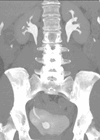

Case 1 1. What is the abnormality and how common is it? 2. What is the embryological origin? 3. With what other conditions can this be associated? Case 2 1. What is the diagnosis and how common is it? 2....